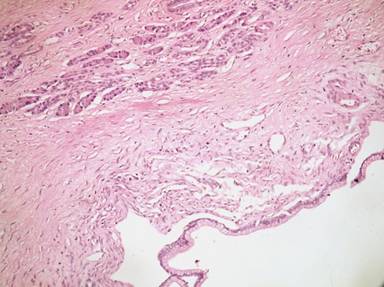

On macroscopic examination the mucosal surface of the colon showed a pedunculated polypoid growth measuring 6x5x2 cm. Outer surface of growth was bosselated and smooth. Cut section of growth showed multi-loculated cystic areas filled with mucin separated by solid areas. Histology (Figure 3). showed mucosal granulation tissue and growth composed of cysts lined by columnar mucinous epithelium with basal mildly anisomorphic round to oval nuclei and abundant pale cytoplasm with apical mucin. At places the cysts showed small papillary projections in the lining epithelium displaying low to high-grade dysplasia with loss of polarity. The sub-epithelial spindle cells stroma was ovarian-like, dense and cellular. The stalk and base of the tumor showed ectopic pancreatic tissue composed of pancreatic acini, islet cells and ducts. No invasive tumor was present. Intra-operative biopsy from the desmoplastic tissue showed fibro-adipose tissue, no evidence of malignancy was noted.